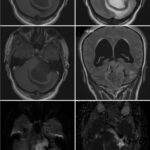

Neurosurgery and neuroradiology always go hand in hand. This little weekly activity is going to enhance the scan reading skills of our audience in an interactive way. Waiting for the answer for a week will keep the curiosity alive and will keep our target audience hooked to the website. It will prove to be a seamless share of knowledge and reading skills.

Dr. Saqib Kamran Bakhshi started the PANS Weekly Image Challenge in 2022, and his creativity and efforts made it a popular activity; engaging trainees and consultants in Pakistan and abroad.